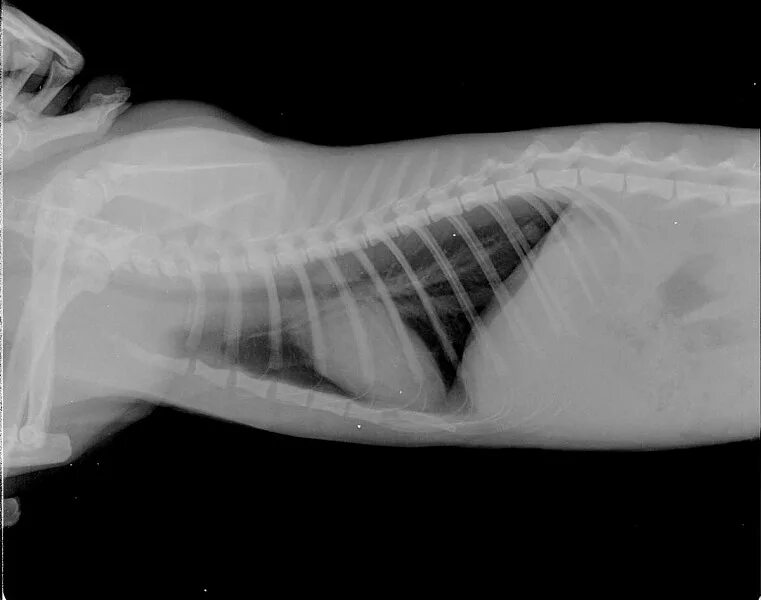

Астма у кота